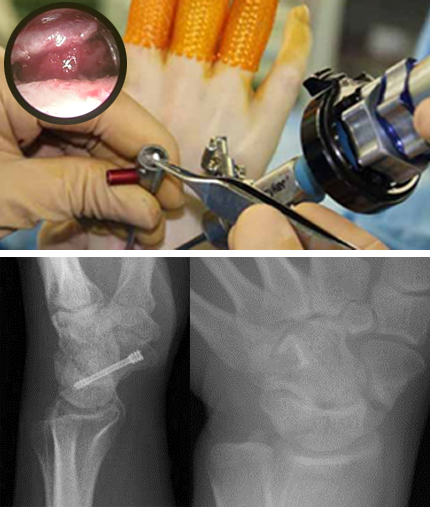

手関節鏡(2.3mmの内視鏡)を用いた低侵襲手術を行っています。従来の大きな皮切を用いた手術に比べて術後の疼痛が軽く、傷跡が目立たないのが特徴です。

【対象疾患】

- TFCC損傷

- 母指CM関節症

- ガングリオン

- 舟状骨偽関節 等

上写真:術中写真

下写真左舟状骨偽関節 左:術前 右:術後